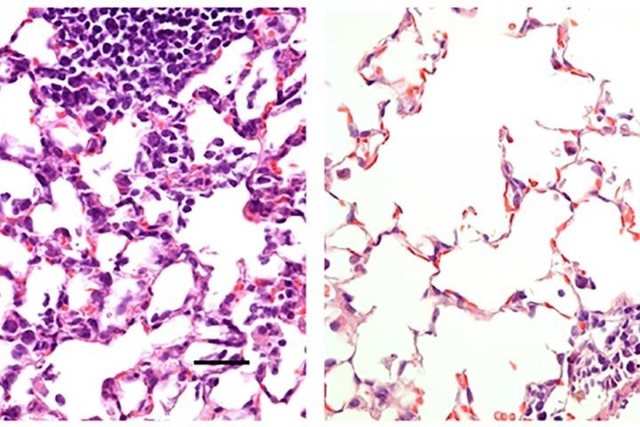

Los investigadores compararon esta vacuna administrada a los ratones de dos maneras: en la nariz y a través de una inyección intramuscular. Mientras que la inyección indujo una respuesta inmune que previno la neumonía, no previno la infección en la nariz y los pulmones. Tal vacuna podría reducir la gravedad de COVID-19, pero no bloquearía totalmente la infección o evitaría que los individuos infectados propagaran el virus. Por el contrario, la vía de administración nasal previno la infección en las vías respiratorias superiores e inferiores (la nariz y los pulmones) lo que sugiere que los individuos vacunados no propagarían el virus o desarrollarían infecciones en otras partes del cuerpo.